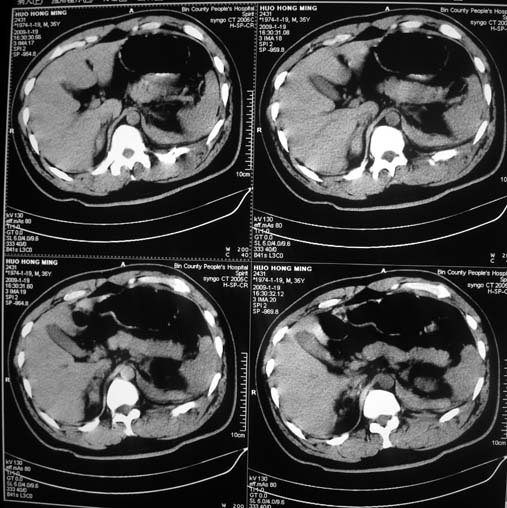

以下是引用余辉在2009-1-20 8:22:00的发言:[br]右侧肾上腺明显增大、边缘不光整,肯定有问题,结合患者病史考虑肾上腺挫伤、伴血肿形成。[br]另左肾后唇包膜下方可见局限性新月形高密度影,考虑肾包膜下出血[br]余同意楼上,建议增强排除脾破列

以下是引用随光逐影在2009-1-20 8:21:00的发言:[br]1)左侧多发肋骨及部分腰椎左侧横突骨折。2)左侧肾旁后间隙及同侧胸腔积血。3)左侧腰大肌肿胀。